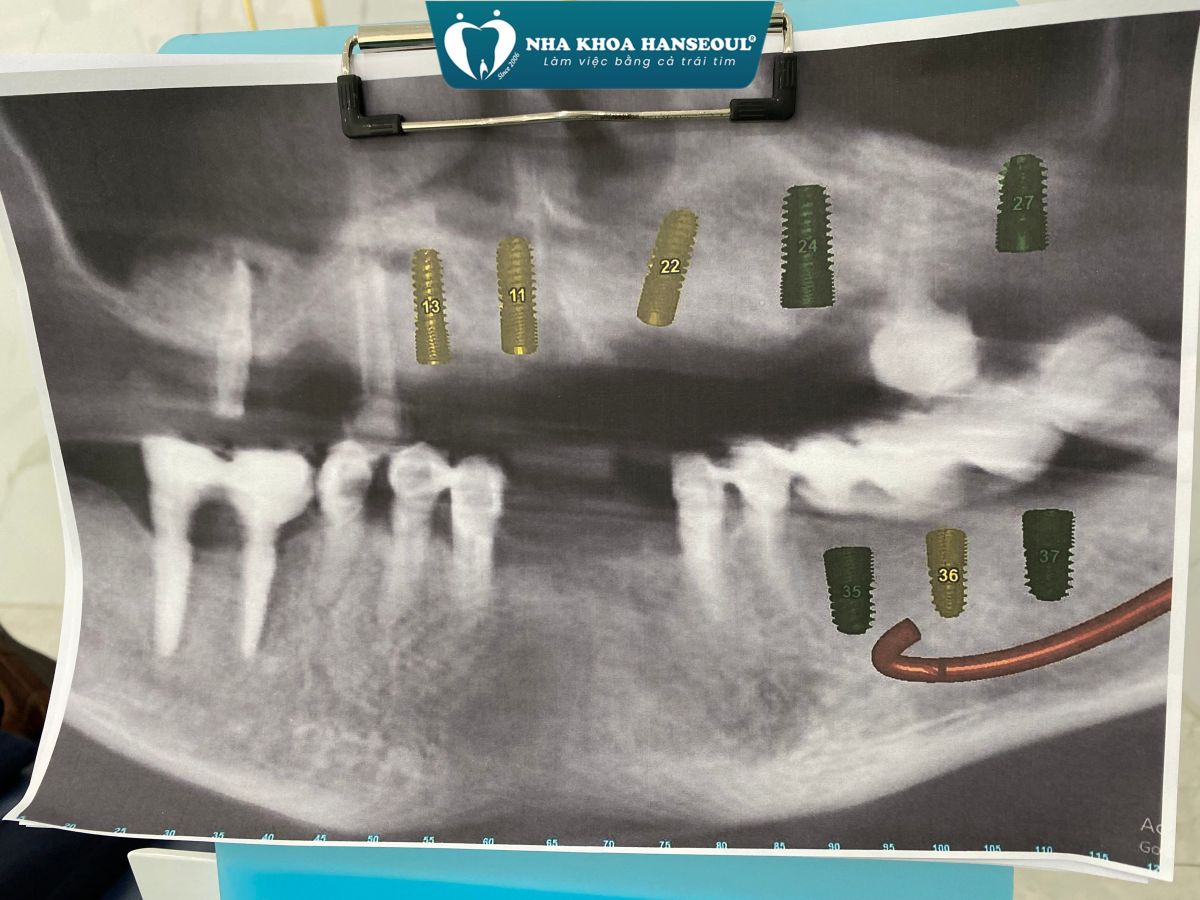

Khi tiếp nhận thăm khám, bác sĩ nhận thấy:

- Hàm trên: chỉ còn lại vài trụ Implant cũ đã được đặt cách đây hơn 10 năm, hiện nay có dấu hiệu tiêu xương quanh trụ, không còn đảm bảo chức năng nâng đỡ phục hình.

- Hàm dưới: nhiều mão sứ và cầu răng đã xuống cấp, lỏng, gãy, gây mất cân đối khớp cắn và ảnh hưởng đến khả năng ăn nhai.

- Xương hàm có dấu hiệu tiêu và mỏng, cần được đánh giá kỹ qua phim CT ConeBeam 3D để xác định có cần ghép xương, nâng xoang trước khi cắm trụ mới.